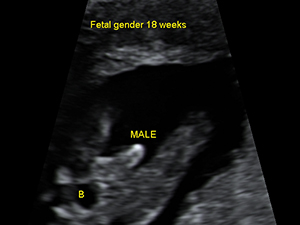

Male genital organ (arrow) at 18 weeks

Male genital organ (arrow) at 18 weeks Gender - Female